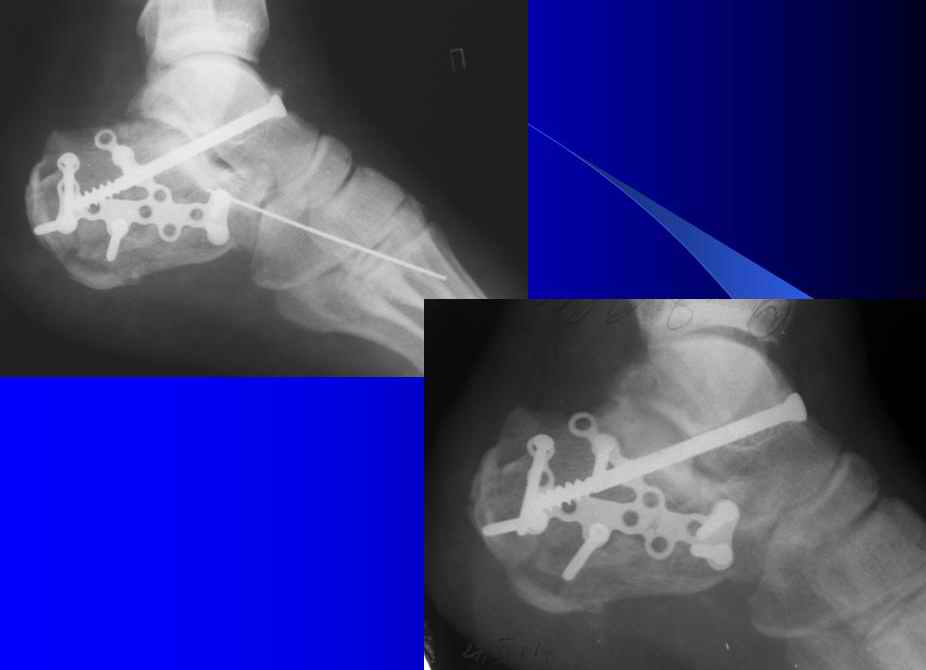

Уважаеемый коллега.Слева ситуация достаточно не сложная.Суставной фрагмент вклинился в тело.Необходимо наружным доступом освободить отломки,поднять суставной фрагмент и фиксировать пяточной пластиной LCP.

Результат посылаю отдельно.На предыдущих рент. видна репозиция.

Справа ситуация сложнее так как имеется помимо перелома имеется вывих тела пяточной костиПоэтому даже если удастся достигнуть хорошей репозиции необходимо сделать первичный подтаранный артродез.Иначе кость не будет держать в своём ложе.Но пластина нужна обязательно чтобы восстановить форму пятки.С уважением Дрягин

Otkritaya repositsija, fixatija plastinoj. Sprava podtaranniy artrodez.